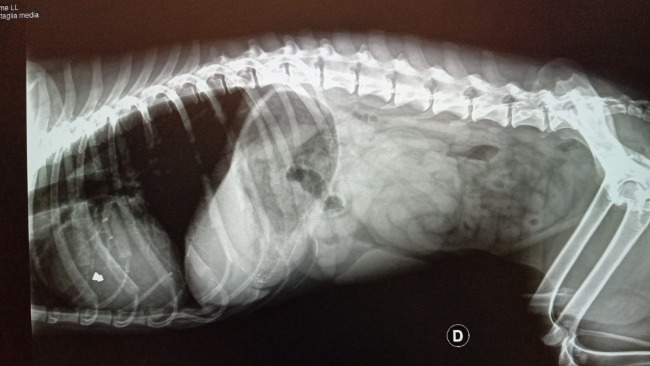

Tolek nie jest jeszcze staruszkiem – weterynarze twierdzą, że ma 7-9 lat. Do tego jest mega silnym pieskiem, bo jak się okazało na prześwietleniu rentgenowskim – musiał być kiedyś postrzelony, a pocisk zatrzymał się w żebrach, blisko aorty.